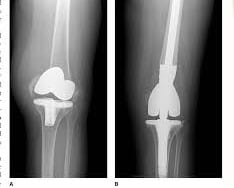

Orthopaedic Trauma Surgeons are unique in that they specialize in complex injuries to bones, joints and soft tissues (like muscles, tendons and ligaments) throughout the entire body. Many orthopaedic specialists specialize in just one body part. Others may provide more general care but won’t treat more acute fractures, which are physically more difficult to fix. Orthopaedic trauma physicians, however, receive training in the field of orthopaedic surgery with a special focus on the treatment of fractured bones and joint realignment to promote the safe recovery and return of functionality to injured body parts. So, they often treat patients with multiple broken bones, compound fractures and fractures near a joint (like a hip or knee).Orthopaedic trauma surgeons are able to follow patients through all stages of recovery and enlist the help of other specialists, if needed, to treat complex cases. By maintaining open communication with all providers, they are able to ensure each patient receives the care needed to resume a full and active lifestyle.

The centre of excellence offers extensive expertise in: